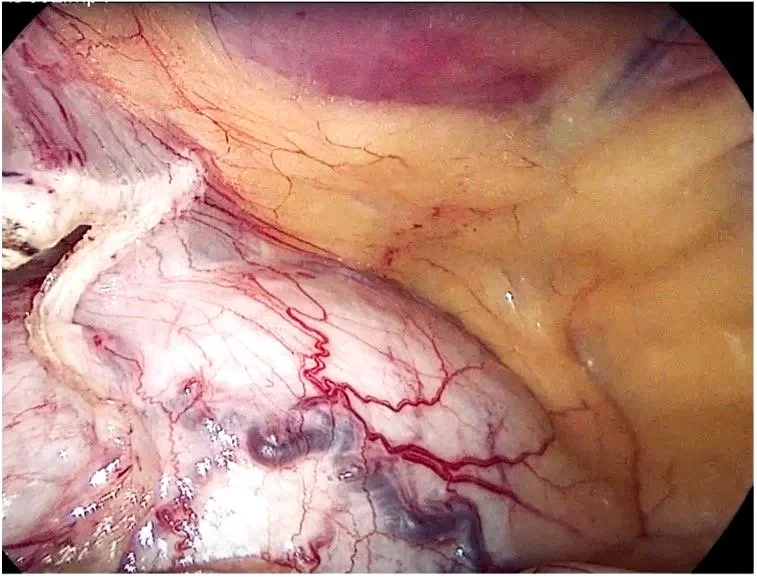

Figure 5. Omental adhesion to uterine fundus, uterus,

left fallopian tube and ovary.

Figure 6. Distended intraperitoneal urinary bladder

(post adhesiolysis).

Examination of the abdomen and pelvis identified normal upper abdominal structures, liver and stomach. The presence of omental adhesions was identified to the uterine fundus, bladder, left adnexa and anterior abdominal wall – most likely the result of Kera’s two previous laparotomies. Adhesiolysis was preformed using a combination of sharp dissection with laparoscopic scissors and an advance bipolar sealing device. An additional 5mm suprapubic port was required to displace the prominent urinary bladder.